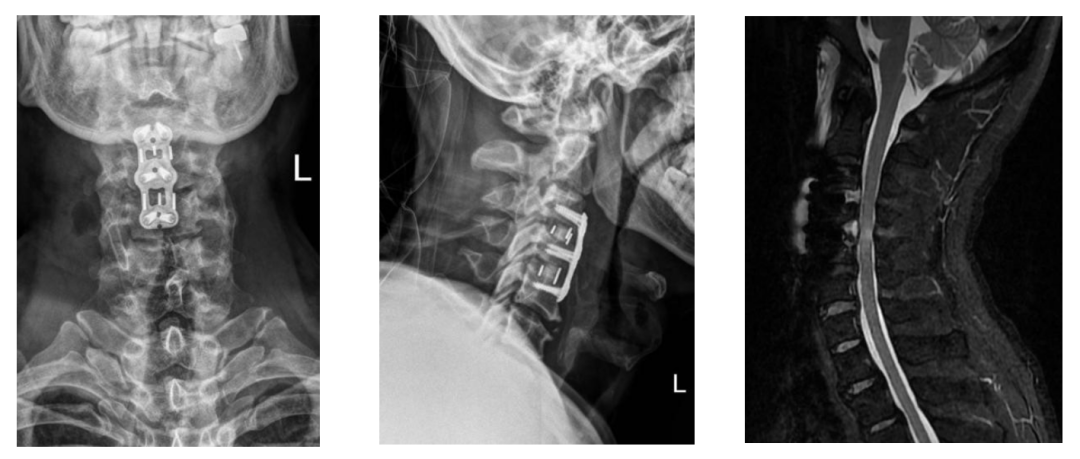

近日,山东第一医科大学附属中心医院中心院区脊柱外科主任医师张庆国团队,紧急救治了一位47岁头颈部外伤患者。看似普通的磕碰,竟让患者突发瘫痪,呼吸、大小便功能也受影响,送至医院后确诊为无骨折脱位型颈脊髓损伤。张庆国与主任刘淑恒、医师张高翔当天便开展急诊手术,1小时左右就完成救治,术后患者神经功能快速恢复,与同类患者相比,神经恢复更加充分且快速,为这类凶险损伤的救治提供了范本。

无骨折脱位型颈脊髓损伤的核心特征的是:颈椎影像学检查未显示骨折或脱位,但脊髓已发生实质性损伤,这种“表里不一”的表现正是其凶险性的关键所在。

对于疑似此类损伤的患者,就医后需尽快完善颈椎磁共振(MR)等相关检查,以明确脊髓损伤情况及压迫来源。医生会根据患者的具体病情,制定个性化的诊疗方案。若符合手术指征,需及时开展手术治疗,手术的核心目标是精准解除脊髓压迫,尽可能保留和恢复神经功能,且在技术允许的前提下,会力求减少手术创伤、降低手术风险。